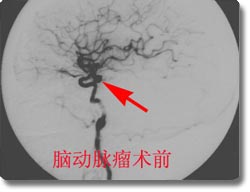

脑血管疾病的治疗

开展了脑动脉瘤、脑血管畸形、颈内动脉海绵窦瘘、脊髓血管畸形的神经介入治疗和恶性肿瘤的次选择性化疗,尤其是对巨大动脉瘤的栓塞成功率达到国内领先水平。同时开展了脑动脉瘤、动静脉畸形、高血压脑出血的手术治疗和血管闭塞性疾病的颅内外搭桥手术、颈内动脉内膜切除术、急性栓塞的溶栓治疗术、血管内支架放置手术,颅内动脉瘤电解可脱性螺旋圈(CDC)治疗,先后收治病人4000余例,积累了丰富的经验,为脑血管狭窄、脑供血不足及脑血栓病人的康复提供了有力保证。介入治疗具有不出血、无感染、损伤小、风险小、恢复快的优点,是脑血管疾病病人的理想选择。2003年,与北京宣武医院强强联合成立了北京市脑血管病中心重庆分中心。2005年成功地承办了第七届全国神经外科血管内治疗研讨会,受到了与会专家的一致赞誉。